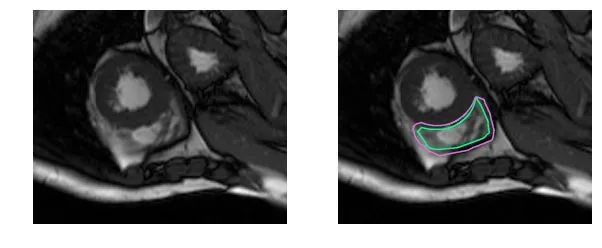

基于FCN网络结构实现左、右心室分割:

Phi V. T.. A Fully Convolutional Neural Network for Cardiac Segmentation in Short-Axis MRI[C]. CVPR 2016.